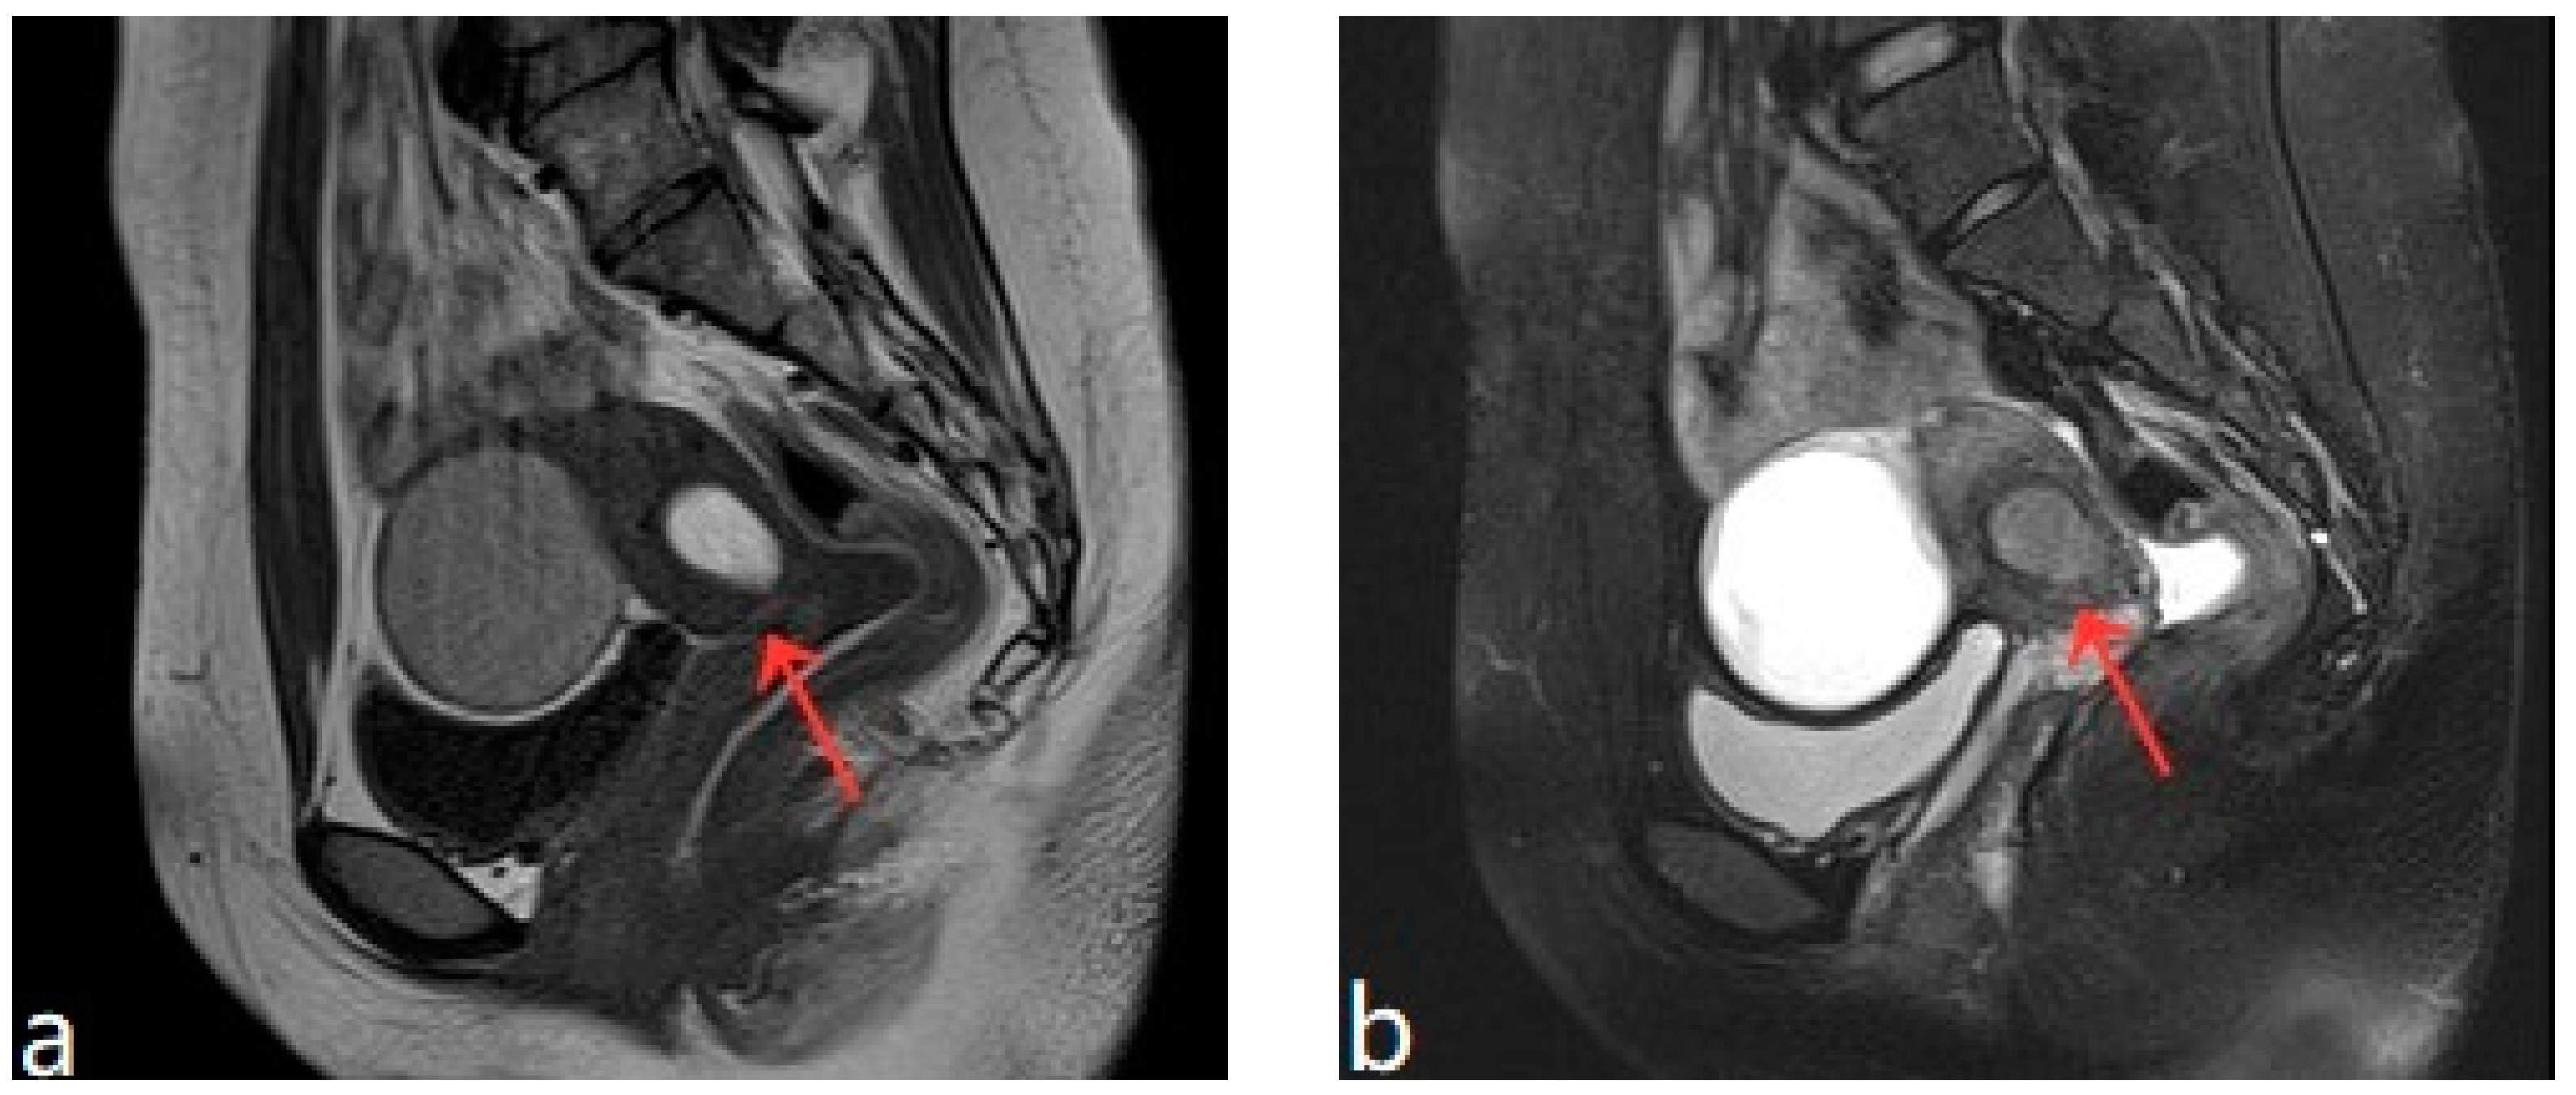

Figure 3.

(a,b) Pelvic MRI shows lesions after HIFU treatment (1st month)(red arrows).